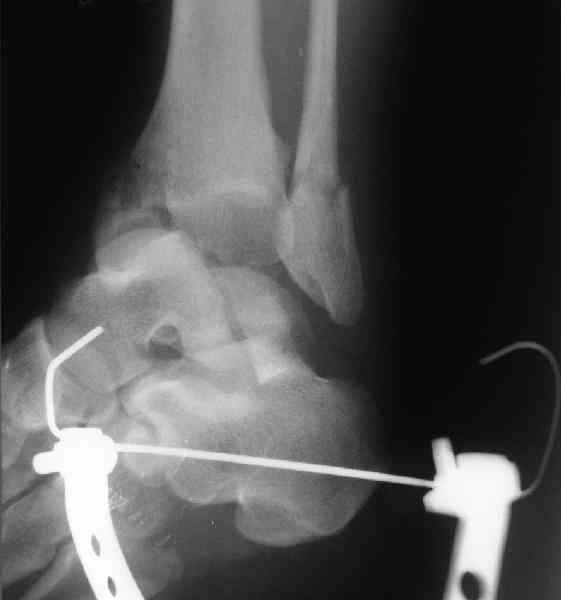

И второй случай из недавней ташкентской практики, (извините за качество ренгенограммы и только в одной проекции) случай падения с высоты (кстати моего друга - известного киноактера) - открытый

смещенный перелом тарана, с переломом переднего края дистального эпиметафиза большеберцовой кости.

При поступлении в приемной сделана первичная обработка с ушиванием открытой латеральной раны и вытяжением за пятку.

Из-за отсутствия времени пришлось оперировать на второе утро, из материала, что имеем на месте, фиксирован двумя шурупами, а третий-это контур сломанного жойстика в 4 мм. На дистальный медиальный конец тибиа antiglide 3.5 мм пластина. Через пару дней выписан и несмотря на предупреждение, самостоятельно начал нагрузку в 4 недели, время не ждет, снимается в боевике в Росийской Федерации.

Djoldas Kuldjanov, MD